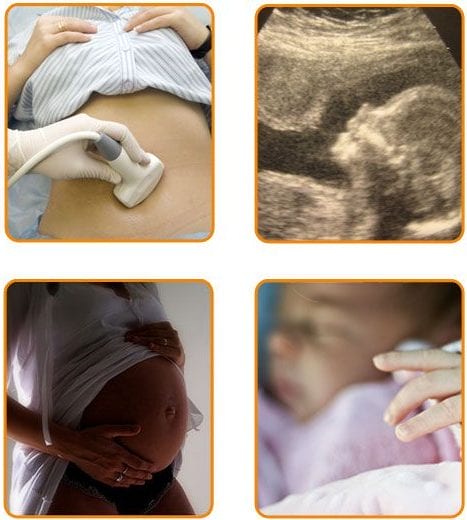

The Final Successful Stage of In Vitro Fertilization

The pregnancy test is done 14 days after egg collection. If this test is positive, an ultrasound follows to confirm the existence of a bag or bags of pregnancy and after that the fetal heartbeats.

The specialized personnel of IVF Centre “Mitosis” is close to the future mother following the progress of the pregnancy.